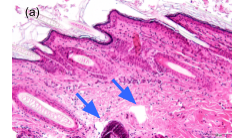

Воздействие короткими импульсами (450пс/380пс) при высокой и стабильной мощности создает лазеро-индуцированный оптический пробой без теплового эффекта